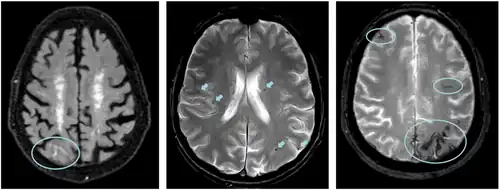

Left: ARIA-E with sulcal effusion (FLAIR sequence)

Middle: ARIA-H with multiple microbleeds (T2* weighted)

Right: ARIA-H with superficial siderosis (T2* weighted)